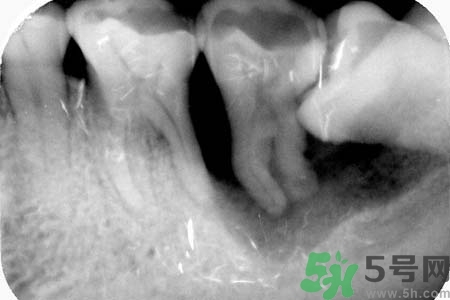

不少人長(zhǎng)了智齒后拍片子顯示牙齒橫著在長(zhǎng),出血這種情況的時(shí)候該怎么辦?智齒橫著長(zhǎng)一定要了拔嗎?關(guān)于智齒橫著長(zhǎng)怎么辦?智齒橫著長(zhǎng)一定要拔了嗎?智齒不疼需要拔嗎?小編為您一一解答。

如果發(fā)現(xiàn)自己的智齒橫著長(zhǎng)了,為了不讓智齒阻生引起其他的危害,我們一定要盡快把橫著長(zhǎng)的智齒拔除,而且不需要鑲牙,拔掉之后有助于身體健康,還可以保護(hù)附近其他牙齒。但是,我們還要重視一點(diǎn),拔智齒是一種牙科門診手術(shù),要求醫(yī)生的技術(shù)水平要比較高,因?yàn)闄M生的智齒,拔除的時(shí)候難度更大,首先要將黏膜切開(kāi),去骨之后才可以拔除的,這不是普通的牙醫(yī)可以把握好的。所以,小編在此提醒各位患者,務(wù)必選擇正規(guī)的牙科醫(yī)院,由專業(yè)的牙科醫(yī)生進(jìn)行拔除手術(shù)。

智齒橫著長(zhǎng)在拔除的時(shí)候需要遵循一些原則。正常情況下,生長(zhǎng)情況沒(méi)有出現(xiàn)異常的智齒盡量要保留下來(lái),不要隨便進(jìn)行拔除。特別是那些生長(zhǎng)了很多年的智齒。只有當(dāng)智齒非正常生長(zhǎng),出現(xiàn)一些臨床癥狀的時(shí)候,才有拔除的需要。而且,在進(jìn)行拔除手術(shù)之前,一定要先拍攝牙片,確定智齒生長(zhǎng)異常再進(jìn)行拔除。還有,發(fā)炎的智齒也必須要拔掉。但是如果炎癥消退,而且沒(méi)有出現(xiàn)復(fù)發(fā)的話,也可以不拔。

智齒橫著長(zhǎng)具有很大的危害,它會(huì)擠壓附近的牙齒,嚴(yán)重時(shí)會(huì)導(dǎo)致整排的牙齒看起來(lái)都不整齊。而且還會(huì)影響到患者的咀嚼功能。智齒阻生跟前牙間會(huì)容易殘留食物殘?jiān)e累細(xì)菌,引發(fā)齲齒或冠周炎。如果一旦出現(xiàn)冠周炎就會(huì)反復(fù)地發(fā)作。智齒橫著長(zhǎng)還會(huì)影響牙齒的咬合,長(zhǎng)期下來(lái)更會(huì)引發(fā)下頜疼痛、夜磨牙等。很多20多歲左右的年輕人,總是覺(jué)得牙齒疼痛,去醫(yī)院檢查都會(huì)發(fā)現(xiàn)是因?yàn)橹驱X橫著長(zhǎng)。但是智齒橫著長(zhǎng)很難察覺(jué),通常都是是引發(fā)了疼痛,患者才會(huì)開(kāi)始所察覺(jué)。